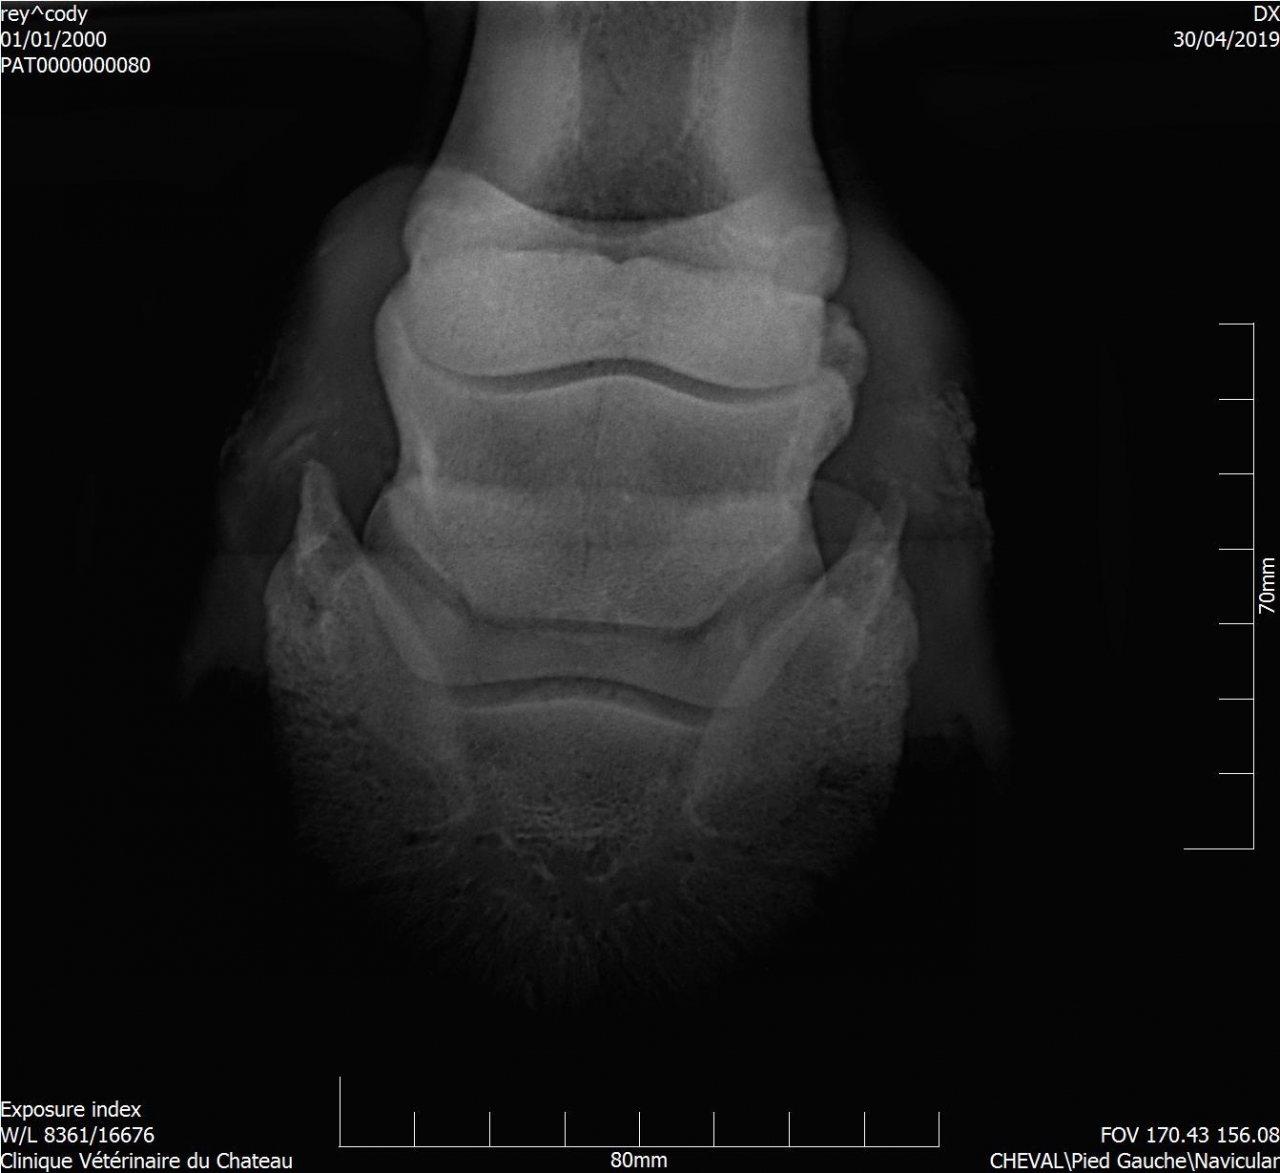

| Dire merci | Voici le compte-rendu du véto : Examen général: L’examen locomoteur au pas et au trot en ligne droite ne met pas en évidence de boiterie. Le cheval pose l’antérieur droit en deux temps : pose d’abord en muraille externe puis en interne. Une boiterie 2/5 de l’antérieur gauche apparait sur le cercle au trot à droite Examens complémentaires : Radiographie : Pieds de face : 3-4 fossettes synoviales sur le bord distal du naviculaire antérieur droit, de profondeur faibles et peu ouvertes. 2-3 fossettes synoviales dont l’une plus ouverte sur le bord distal du naviculaire antérieur gauche Léger pincement articulaire p1-p2 et p2-p3 coté externe visible sur le membre à l’appui. Boulet de face : Petit remaniement osseux au niveau de l’insertion proximale du ligt coll int Boulet et pieds ant droit de profil : ras La boiterie étant trop légère pour préciser la localisation par anesthésie étagée, plusieurs hypothèses sont envisagées. Par ordre d’importance : • Pincement et fatigue articulaire lié au parage ou à une compensation d’une légère entorse boulet • Entorse du boulet • Début syndrome podotrochléaire Message édité le 14/05/19 à 18:37 |

| Dire merci | Les radios ont été faites hier, il y a clairement un souci sur le naviculaire antérieur droit (le véto m'a montré le cliché sur l'écran). |

| Dire merci | Dans le cas que je connais bien, l'os naviculaire est en sale état. Mais la douleur et donc la boiterie, vient du tendon qui s'enflamme en frottant sur cet os "rugueux" (je ne connais pas le terme exact). Donc avec un parage adapté, un pré plat (très important), peu de travail et surtout éviter le galop (je parle toujours du cas de Kachou) ainsi que tout travail en cercle, on peut donner du confort au cheval. Mais il n'est pas guéri, hélas, et il suffit de peu de choses pour qu'on le voie à nouveau boiter. |